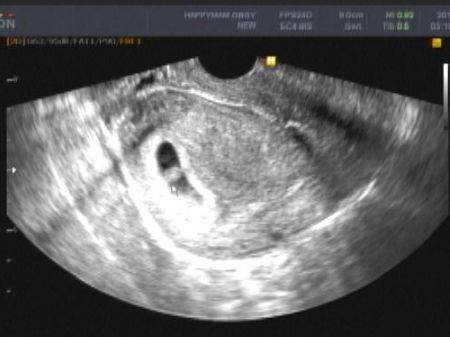

胎儿的心跳一般会在

怀孕后6周左右被检测到

这什么概念?

此时宫内还只是个胚胎

豆子一般大小

大约Emmm...6毫米长吧

对孕妇而言

这时例假才推迟两周

这对很多例假不规律的妹子而言

是多么稀疏平常的事情

而且这个阶段还没有孕吐反应

大部分人是察觉不到怀孕的啊!